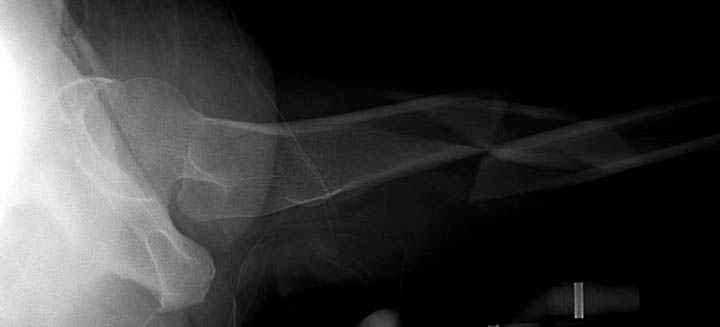

Среди русскоговорящих коллег Ортофорум стал одним из мест, где многие из нас черпают знания для решения своих ежедневных проблем в виде практических советов и обмена опытом. Кроме таких советов, Ортофорум стал источником новых познаний среди ортопедов, особенно по редко встречающимся состояниям в ортопедии. Продолжая традицию, я хотел бы представить редко встречающий случай перелома бедра у больного с гемофилией. Больному 42, гемофилия типа А, из истории упал с высоты около 1,5 метра, переправлен из другой больницы. По происхождению мексиканец, 10 лет назад по поводу артроза пр. коленного сустава в Мексике сделано протезирование, которое закончилось ампутацией выше коленного сустава. При поступлении бедро напряженное, сосудистых и неврологических расстройств нет. На рентгенограмме оскольчатый перелом бедра с вовлечением проксимальной спирали в шейку бедра. Хотели бы знать тактику ведения подобных больных и на что надо обратить внимание? Djoldas Kuldjanov, MD Department of Orthopedic Surgery St. Louis University Medical Center

Учитывая, что случай ургентный, больной поступил вечером, не стали делать вытяжение и срочно провели операцию по фиксации перелома бедра антеградным штифтом Versa Nail от DePuy.

Для профилактики дальнейшего раскола в шейке предварительно во время проксимального рассверливания спереди и сзади провели временные спицы, которые в дальнейшем были заменены на шурупы (miss nail method)